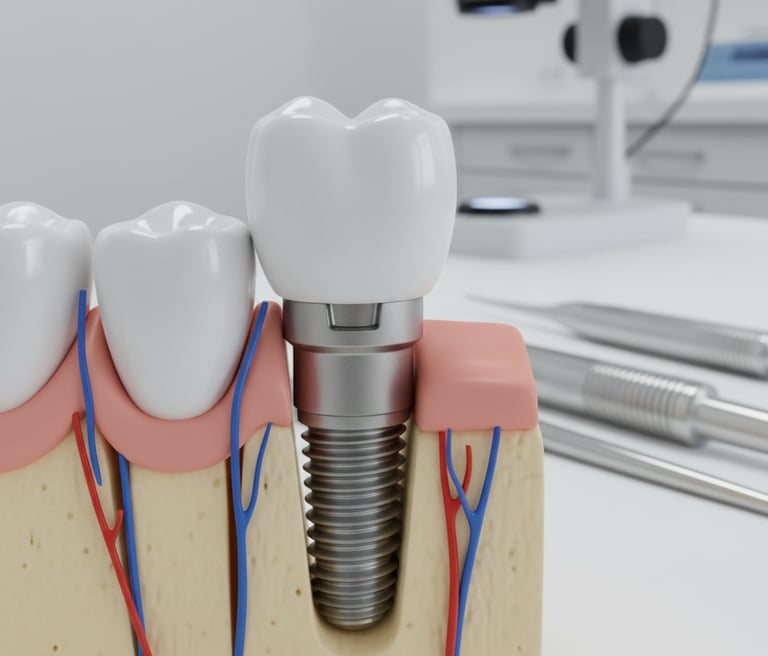

¿Es seguro un implante dental?

Ofrecemos servicios de prótesis, coronas e implantes dentales en David, Chiriquí, con un equipo especializado y un laboratorio dental digital propio para garantizar la calidad y tiempo de entrega de los tratamientos.

Ofrecemos servicios de odontología general, especialidades en restauraciones, coronas, potesis, implantes dentales y laboratorios dental digital, en David, Chiriquí

Planes de ortodoncia, protesis, coronas e implantes dentales, con atención integral.